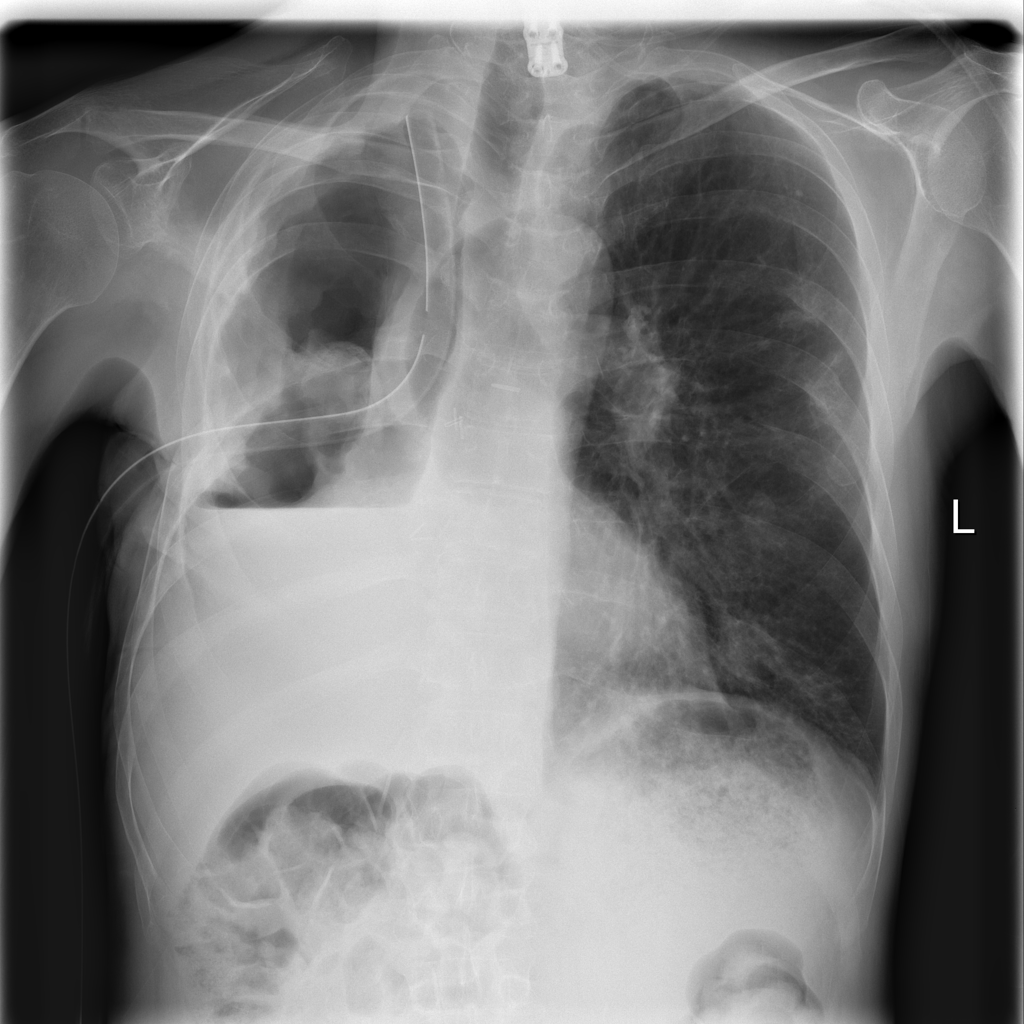

PAT-0ABD · IMG-000Hernia

PAT-0ABD · IMG-000

PA